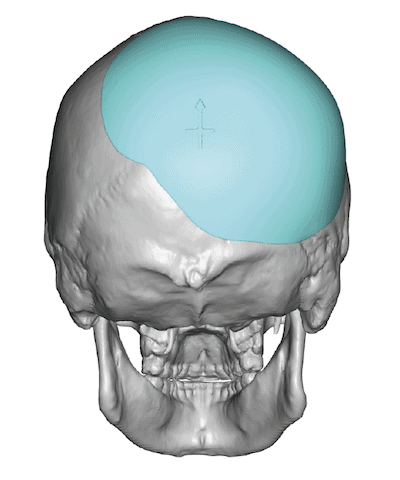

Patient 28

Desire for rounder shape to the top of the head from a congenital parasagittal deficiency skull shape.

Custom skull implant designed to fill in the parasagittal deficiencies.

Desire for rounder shape to the top of the head from a congenital parasagittal deficiency skull shape.

Custom skull implant designed to fill in the parasagittal deficiencies.